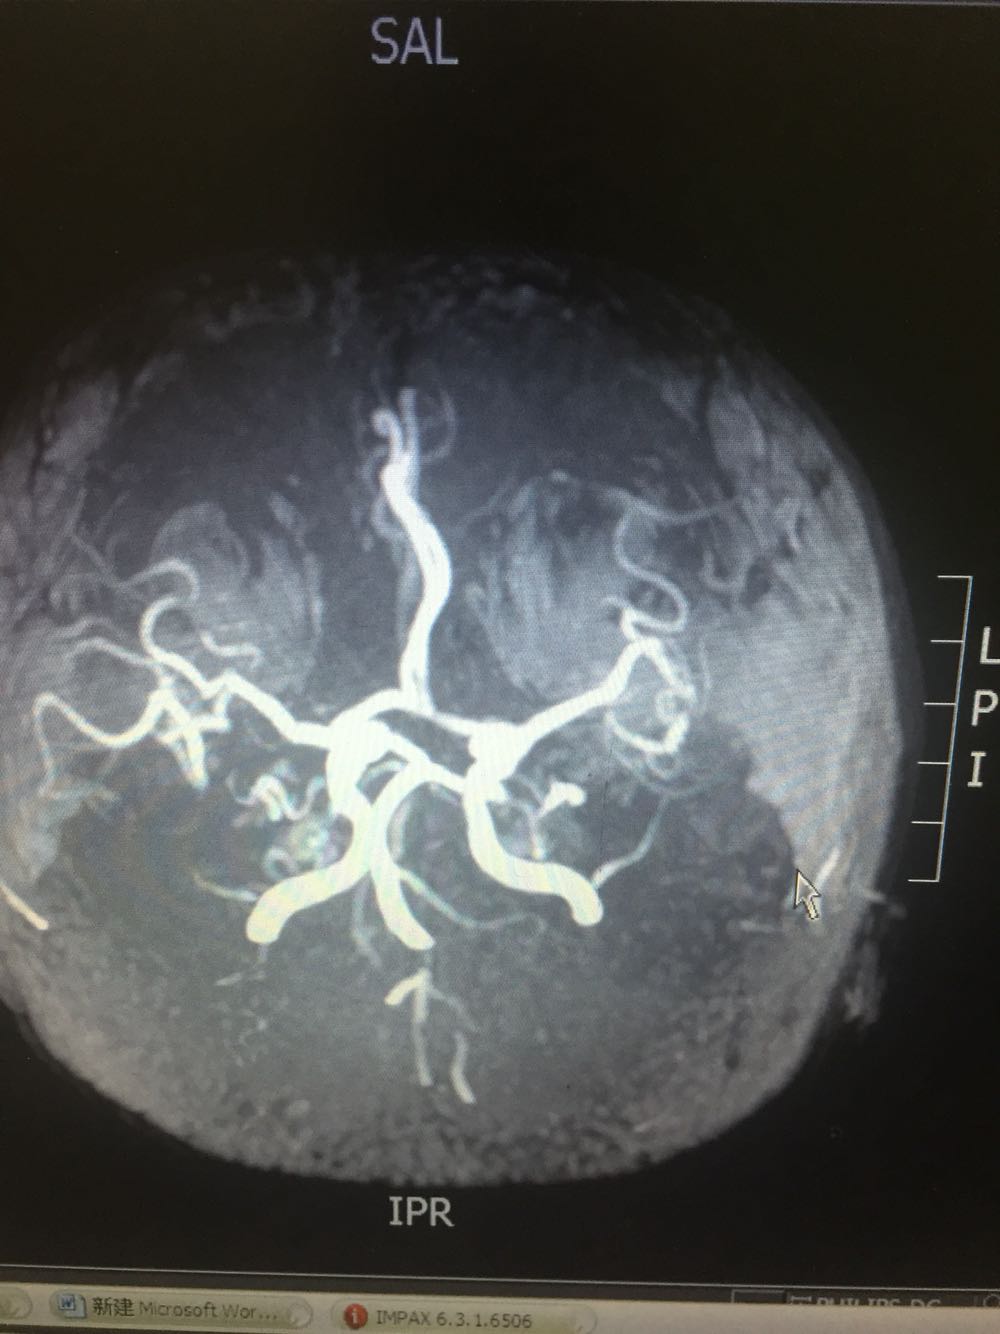

患者于入院后第二日晨起时突发左侧肢体无力伴抽搐发作,查体:神志模糊,言语含糊,双侧瞳孔等大同圆,对光发射存在,左侧肢体肌力3级,左下肢Babinski(+)Chaddock(+) 不伴有尿便失禁。给予安定肌肉注射,急检血凝及头CT。血凝、头CT回报未见明显异常。患者发病1.5小时与家属沟通建议溶栓治疗,家属同意。患者体重约75kg。给予6mg爱通立静脉推注,随后60分钟内爱通立54mg静脉滴注。患者恢复良好,肌力恢复正常。查头DWI示:右侧侧脑室后脚可疑新发梗死。